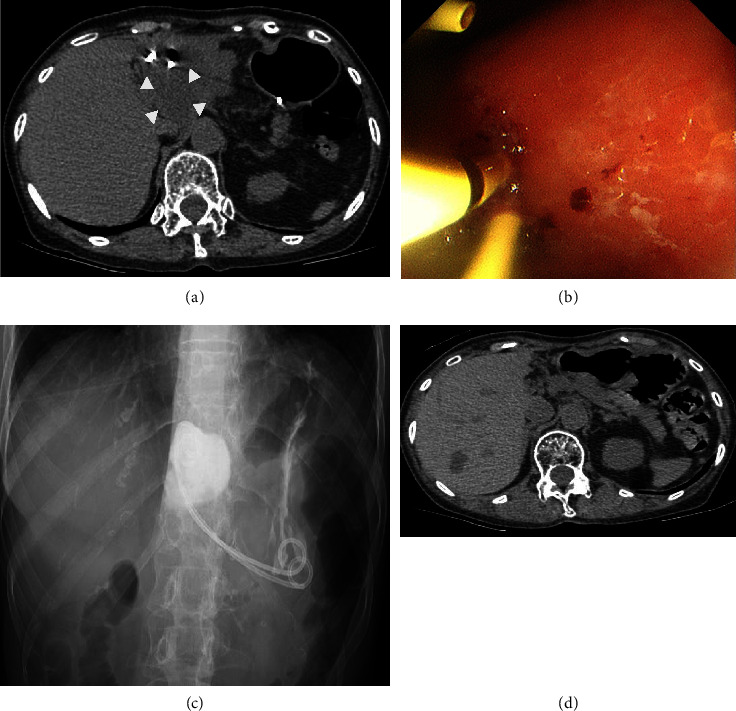

A liver cyst is hepatic fluid-filled cavities often detected in clinical surveillances such as a health examination. Although the liver cyst is usually asymptomatic and observed without any therapeutic intervention, it can be symptomatic and needs treatment due to its enlargement, hemorrhage, and infection. A 74-year-old woman presented with upper abdominal pain and a huge liver cyst in the left lobe. Several examinations including image findings revealed that the symptom could be derived from the liver cyst. Although there is no definite guideline of treatment for symptomatic liver cysts, percutaneous ultrasound-guided drainage with sclerotherapy or surgery is often selected. Because of anatomical accessibility to the liver cyst and the patient's wish, we performed endoscopic transgastric drainage with insertion of both an internal stent and an external nasocystic tube. Sclerotherapy with minocycline hydrochloride was performed through the nasocystic tube, and the liver cyst shrunk completely without any complications. This is the first reported method of administering minocycline hydrochloride through a nasocystic tube, which can be a therapeutic option for patients with symptomatic liver cysts.

Abstract Image